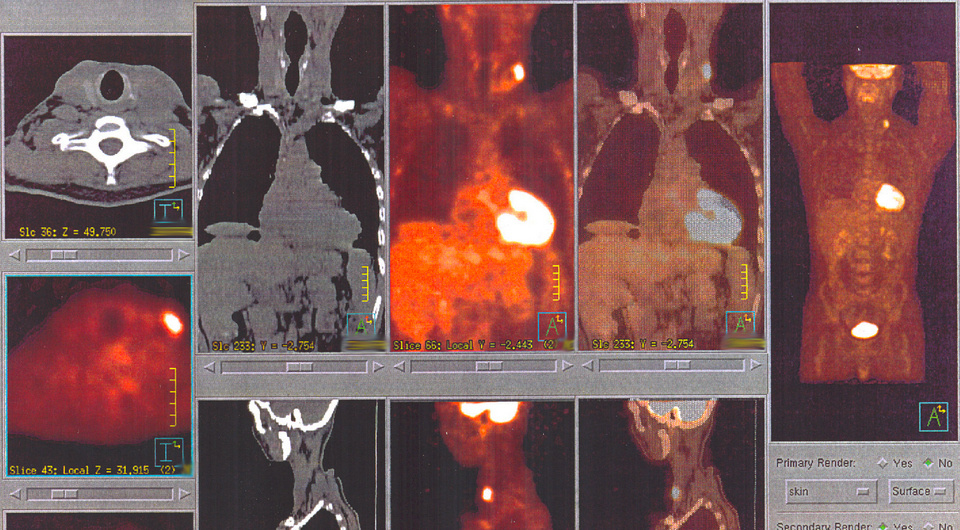

Петер Строугал (Peter Strouhal) с коллегами по британской сети клиник лучевой диагностики Alliance Medical Limited с филиалами в семи странах провел ретроспективный обзор серии случаев и пришел к выводу, что прием агонистов рецепторов глюкагоноподобного пептида-1 (ГПП-1), типа семаглутида, может искажать результаты ПЭТ-КТ с ¹⁸F-фтордезоксиглюкозой (ФДГ). Исследователи заново проанализировали ПЭТ-КТ-сканы онкологических пациентов своей сети, принимавших агонисты ГПП-1, сравнили их с ожидаемым физиологическим поглощением ФДГ и оценили наряду с имеющимися публикациями. Особое внимание уделяли затруднениям интерпретации, которые могут повлиять на принятие клинических решений. Результаты были представлены (тезис OP-802) на 38 ежегодном конгрессе Европейской ассоциации ядерной медицины EANM 2025. В ходе анализа был выявлен ряд случаев атипичного захвата ФДГ в местах локализации возможных патологических очагов, который мог привести к диагностическим ошибкам. Они соответствовали имеющимся сооб

В ходе анализа был выявлен ряд случаев атипичного захвата ФДГ в местах локализации возможных патологических очагов, который мог привести к диагностическим ошибкам. Они соответствовали имеющимся сообщениям о случаях в медицинской литературе и включали повышенное накопление метки в скелетных мышцах, миокарде и бурой жировой ткани, напоминающее злокачественный рост или воспаление. В сумме это свидетельствует о необходимости проявлять повышенное внимание к клиническому контексту и медикаментозному анамнезу пациентов при интерпретации ПЭТ-КТ с ФДГ.